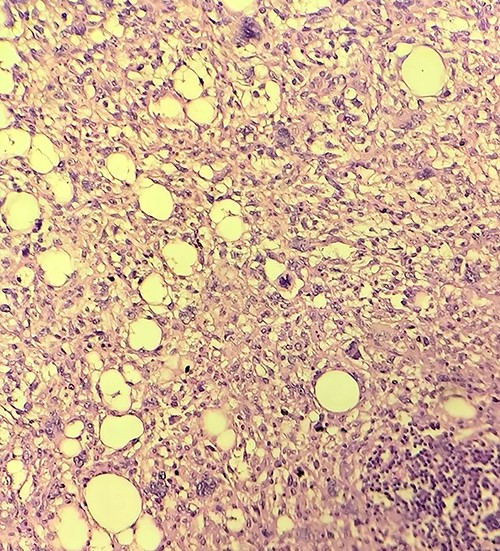

Gross examination revealed large lobulated mass of size 12 cm × 10 cm × 7 cm, weighing 817 g. The cut section showed yellow soft to firm areas with some hemorrhagic areas. Eosin and hematoxylin stain revealed area of lipoblast, pleomorphic cell, mitotic figures with multiple areas of necrosis (Figs 4, 5 and 6). Immunohistochemical reaction showed positivity for S-100 protein, mouse double minute 2 (MDM-2), cyclin-dependent kinase 4 (CDK4) and p16 which helped us differentiate it as dedifferentiated liposarcoma.

Liposarcomas are divided into myxoid, pleomorphic, well-differentiated, dedifferentiated and round cell type [1]. Myxoid variety is the commonest of the liposarcoma found in 50% of the cases [8]. Dedifferentiated liposarcoma is a pleomorphic/undifferentiated sarcoma mixed with well-differentiated liposarcomas exhibiting wide spectrum of morphology [3, 9]. Dedifferentiated liposarcoma is often detected as metastatic or recurrent lesions rather than primary lesion, which is rare as in our case [9]. Of the various immunohistochemical examinations MDM2 and CDK4 show better sensitivity and specificity of 97% and 92%, and 83% and 95%, respectively [10]. Also, S-100 helps in distinguishing liposarcomas from malignant fibrous histiocytoma [11].